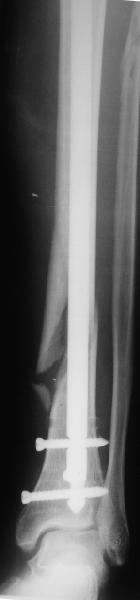

[Ortho] неправильно фиксированный перелом

Все наши сомнения связаны с тем, что этих незначительных погрешностей

(небольшой вальгус, неглубоко пробит гвоздь, мало запирающих винтов в

дистальном отломке) не одна, а несколько и вместе они могут

значительно осложнить дальнейшую жизнь пациенту. В нашей практике были

подобные случаи, при которых после разрешения полной нагрузки либо

начинала увеличиваться деформация, либо происходил перелом гвоздя по

ближайшему отверстию. Кроме того, при диафизарных переломах,  имея в

арсенале надежный фиксатор, нет никакой необходимости вынуждать

пациента ограничивать нагрузку на ногу в течении 2-3 месяцев.

Взвесив все <<за>> и <<против>> мы приняли решение и выполнили

реостеостинтез: выбили гвоздь до линии перелома, провели отклоняющую

спицу, забили обратно гвоздь и заблокировали внизу 3-мя винтами,

вверху одним. Вся операция заняла меньше часа. Сегодня пациент ушел от

нас домой с полной нагрузкой на ногу.